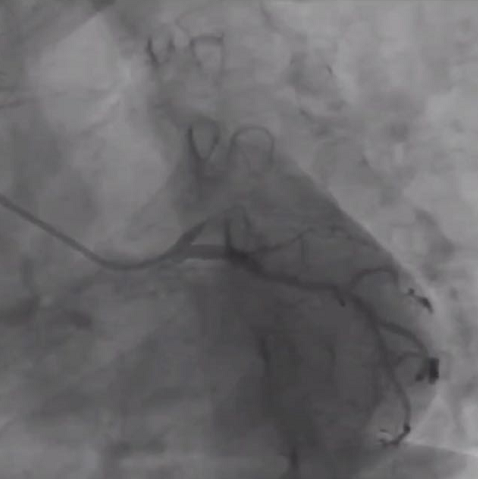

云南圣约翰医院邹云丞教授分享的病例为一名73岁男性患者,冠脉造影示LAD自D1开口闭塞,但闭塞段不长;RCA全程弥漫病变,向LAD提供逆灌,但无理想侧支。于是,手术过程中术者首先启动正向策略,导丝升级后 Gaia 2导丝成功进入远端真腔,但微导管和1.5*10mm小球囊无法跟进;随后术者换用1.0*10mm Firefighter™球囊行爆破技术,成功开通正向通道,前向血流恢复,遂在球囊预扩张后成功植入了支架。第二例病例同样是导丝通过后微导管无法跟进的LAD CTO病例,对于该病例术者选择使用1.0*10mm Firefighter™球囊不断掘进,成功开通闭塞病变。

第一例LAD自D1开口闭塞病例

第二例LAD近段CTO病例

复旦大学附属中山医院张峰教授认为,对于这种有前向微通道的高阻力病变,导丝通过较为容易,但后续微导管和球囊跟进则很困难。在这种情况下,1.0mm规格的Firefighter™球囊有很大用处,无论是主动爆破还是掘进,均可以达到“曲径通幽处,禅房花木深”的效果。